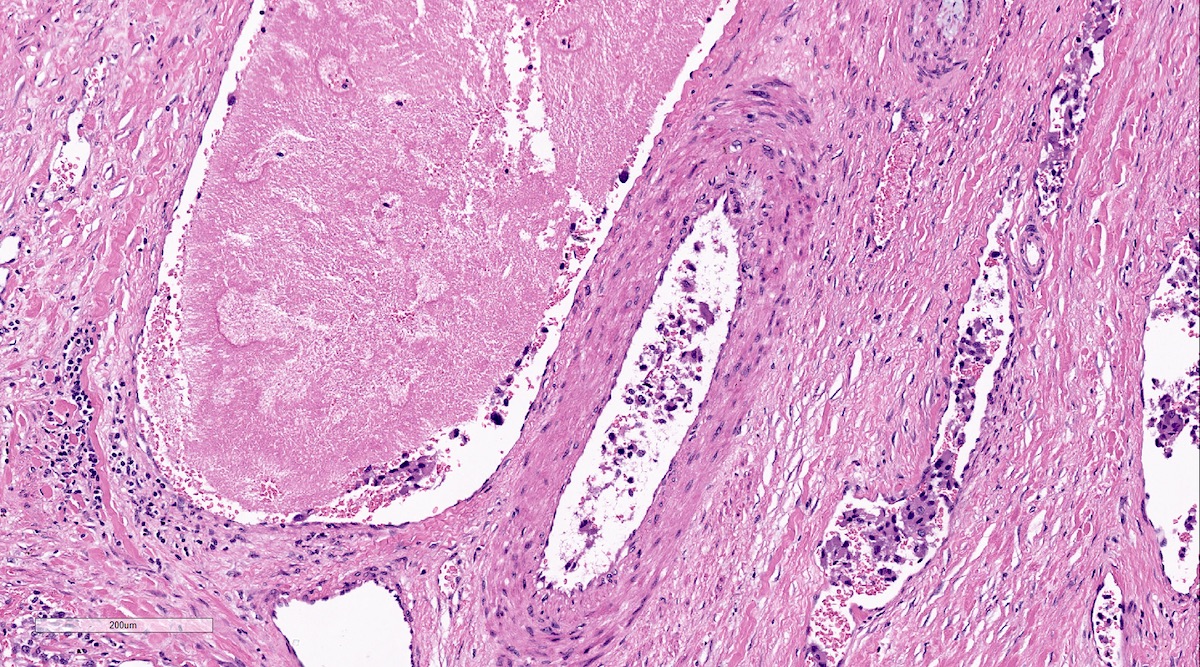

Microscopic (histologic) description

- Necrosis is unusual except in patients who have undergone preoperative tumor embolization

Microscopic (histologic) images

Contributed by Luvy Delfin, M.D. and Sylvia L. Asa, M.D., Ph.D.

- Considered histological parameters: histologic pattern, cellularity, comedo type necrosis and capsular / vascular invasion